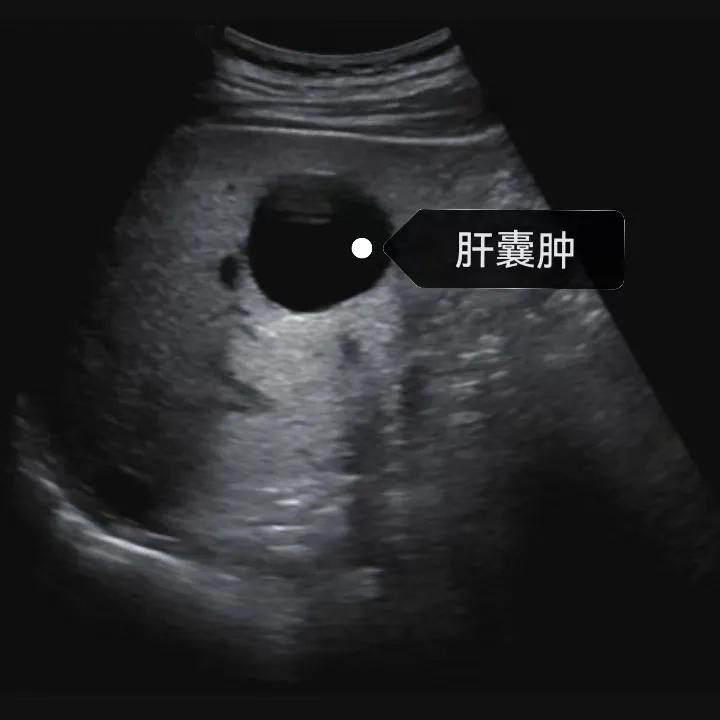

超聲通常是診斷肝囊腫的首選方法,彩超對(duì)肝囊腫的檢出率可達(dá)98%,<1cm的囊腫也可檢出。肝囊腫常表現(xiàn)為圓形或橢圓形無(wú)回聲,包膜光滑完整,邊界清晰,可有側(cè)壁回聲失落征象,后方回聲增強(qiáng)。病程長(zhǎng)、囊腫較大者或囊內(nèi)有過(guò)出血、感染者,無(wú)回聲腔內(nèi)可見(jiàn)少量絮狀回聲漂浮。超聲對(duì)肝囊腫的診斷準(zhǔn)確而靈敏,且方法簡(jiǎn)單、無(wú)創(chuàng)、費(fèi)用低、可重復(fù)性高,因此常常被作為首選。